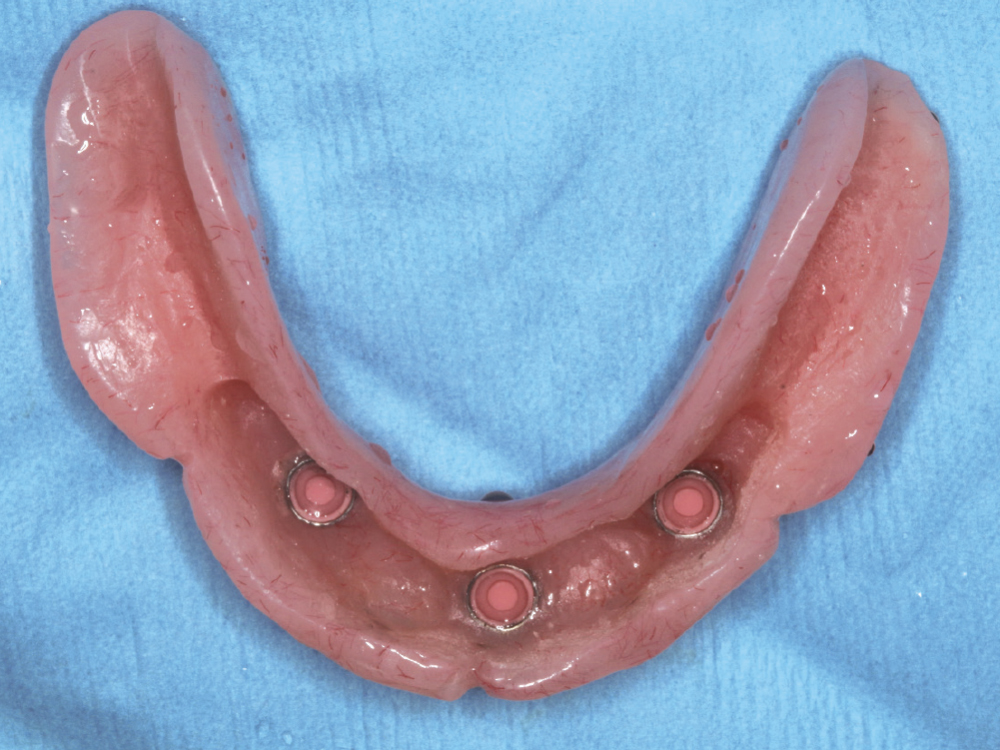

CASE REPORT NO. 1

Freestanding Locator Attachments

Overdentures offer the esthetics of traditional dentures with better retention.